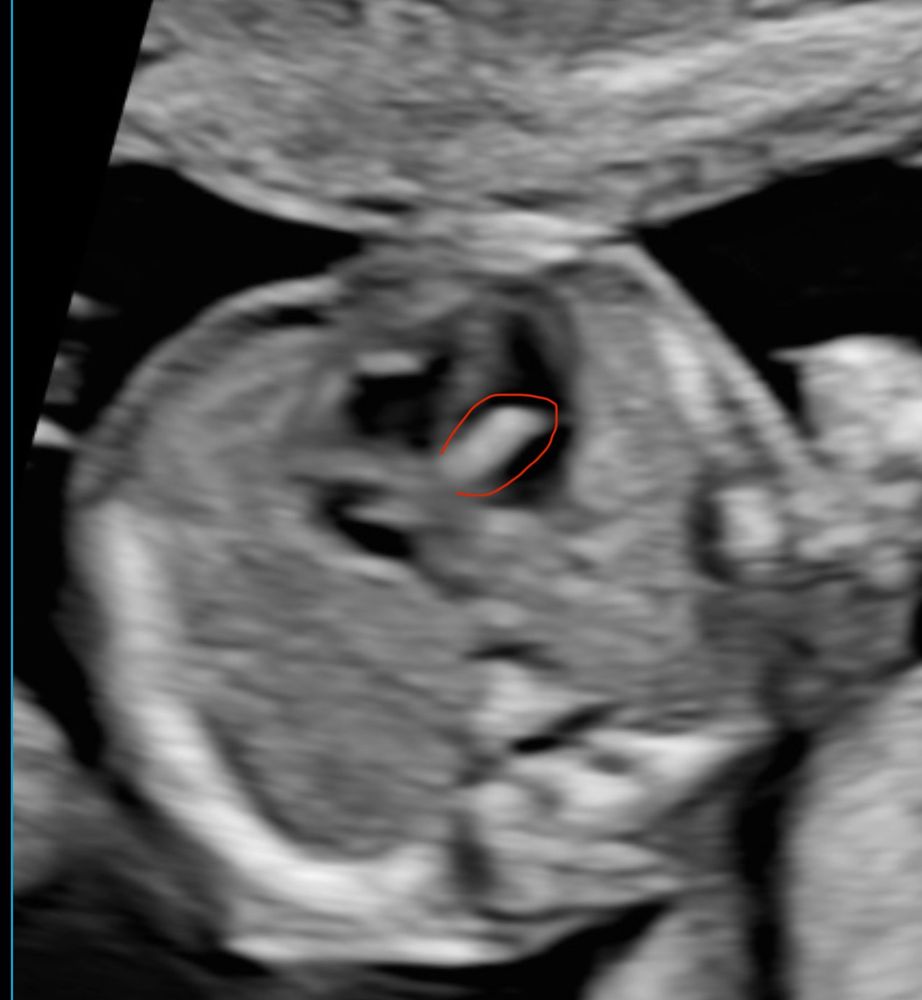

Анализы, скринингиДевочки. Была на узи в 17 недель 3 дня. Гинеколог увидела что-то на сердце , сказала что видит (накипь) (это с нидерландского языка перевод) в сердце , внизу прикрепила фото (я обвела красным то что им не понравилось ) . Она еще позвала другого гинеколога и они вместе что то долго обсуждали и пришли к выводу что через 3 недели еще раз будут смотреть и наблюдать . Мне сказали не переживать и скорее всего это все пройдет . Но не переживать я не могу. У кого такое было , прошло ли это ? И что это вообще такое

Гиперэхогенный фокус - тоже заметили на втором скрининге, размер был 2,1 мм (в платной клинике 2,9 мм). Это как дополнительная хорда - ничем не вредит ребенку и здоровью: рассасывается к рождению либо к году ребенка.